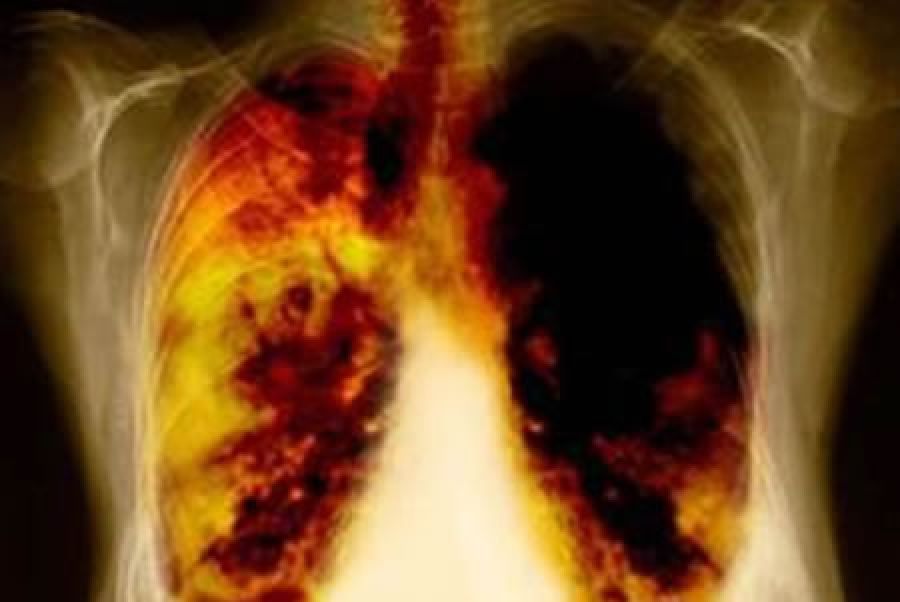

El especialista explicó que cuando el tumor crece e invade el bronquio, los síntomas son tos con sangre; al invadir la membrana que rodea al pulmón, conocida como pleura, puede ocasionar la generación de líquido pleural y, en consecuencia, falta de aire de la persona afectada.

Una vez diseminado el cáncer, el enfermo pierde peso y siente malestar general. Cuando dicha metástasis se registra en hueso -uno de los lugares más frecuente- puede ocasionar dolor, y es el momento en que la persona acude al servicio médico.